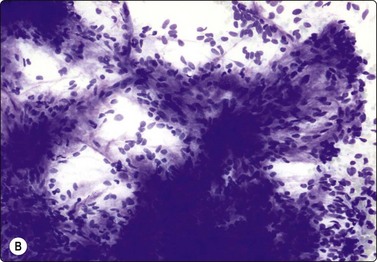

image image image

Fig. 14.9 Cystic eccrine hidradenoma

Loose clusters of basaloid cells with small, dark, uniform nuclei in a background of proteinaceous fluid (A, MGG; B, Pap, IP); (C) Corresponding tissue section (H&E, LP).

The cytology of nodular hidradenoma30-32 and of clear cell hidradenoma33,34 has been described in single cases. A benign skin adnexal tumor from our files, histologically reported as cystic eccrine hidradenoma, is shown in Figure 14.9. The FNB sample was of mucoid fluid which contained clusters of variably cohesive uniform epithelial cells with a moderate amount of cytoplasm and small dark ovoid nuclei. A dual population was not discernible. The cytology was reported as a benign skin adnexal tumor without further specification.